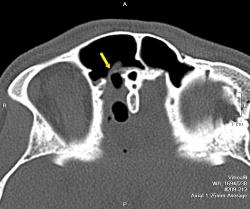

Вот еще один случай. Молодой человек, 20 лет. В анамнезе тяжелая черепно-мозговая травма. Ликворрея.

На снимках виден большой костный дефект (желтая стрелка) в задней стенке лобной пазухи, в полости черепа воздух, который прослеживается в области дефекта в полюсе лобной доли, в большой порэнцефалической кисте с уровнем жидкость-воздух (красные стрелки). Киста связана в передним рогом бокового желудочка, в противоположном желудочке и в третьем воздух (зеленые стрелки). На сагиттальных срезах виден воздух в мостовой цистерне вдоль ската. Поскольку дефект довольно большой, сейчас решается вопрос как лучше его закрыть эндоскопически или через трепанацию.